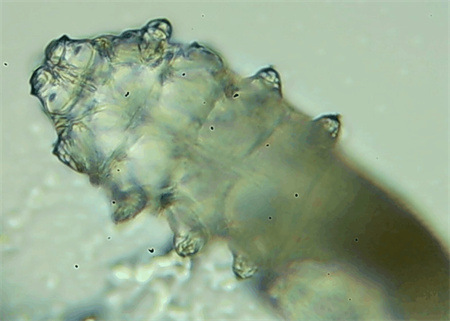

這種螨蟲叫做蠕形螨,他們通常呈乳白色、半透明的細(xì)長(zhǎng)狀,擁有四對(duì)腳。它們跟被子上的塵螨可不是同一種。

這些蠕形螨主要寄生在面部、頭皮、眼睛的睫毛毛囊、睫毛皮脂腺,以及瞼板腺里,以睫毛囊上皮細(xì)胞、腺體內(nèi)脂質(zhì)為食物。因此,即使經(jīng)常換洗床單、衣物,也可能會(huì)有蠕形螨。